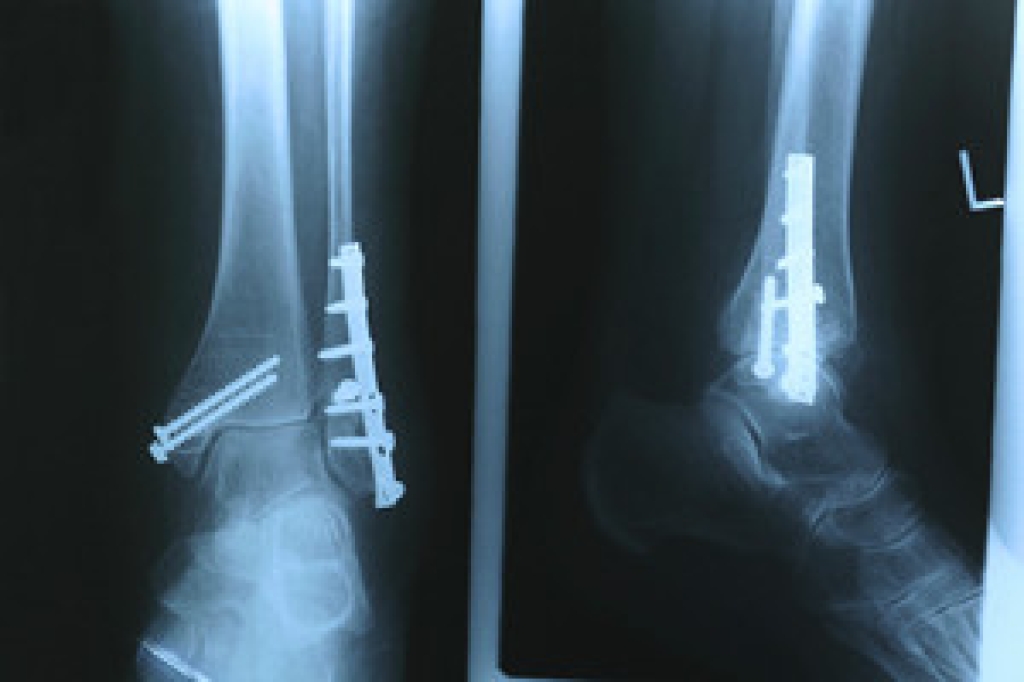

Sports that cause the most ankle injuries are football, basketball, soccer, tennis, and running. Football is a rough sport that can cause, among other things, high ankle sprains. A high ankle sprain is an injury that happens from the outward twisting of the foot or ankle. Basketball can cause Achilles tendonitis, which is a swelling of the Achilles tendon linking the heel bone to the calf muscle. Soccer injuries include ankle sprains and ankle impingement, a condition where bone spurs develop on the ankle bones. Tennis requires players to run fast in a small area and make sudden changes of direction, causing them to be susceptible to stress fractures and ankle sprains. Running can cause similar injuries. If you participate in these sports, it is important to wear proper footwear for the sport you are participating in, warm up properly, and remain alert while at play. It is also suggested that you consult with a podiatrist who will not only be able to help you if injuries to the feet and ankles occur, but also educate you on ways to prevent common injuries.

Sports related injuries are commonly treated using the RICE method. This includes rest, applying ice to the injured area, compression and elevating the ankle. More serious sprains and injuries may require surgery, which could include arthroscopic and reconstructive surgery. Rehabilitation and therapy may also be required in order to get any recovering athlete to become fully functional again. Any unusual aches and pains an athlete sustains must be evaluated by a licensed, reputable medical professional.